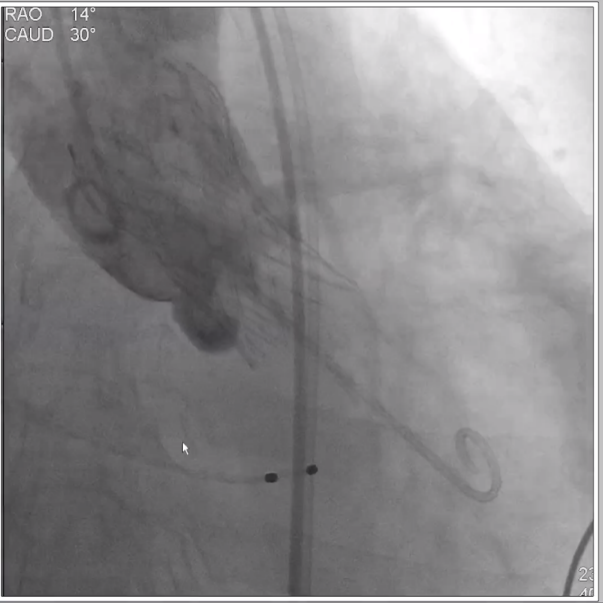

首先进行球囊预扩、造影,判断左右冠开口情况,实际显示冠脉灌注良好,将根据瓣膜植入后情况再决定是否进行冠脉干预,由于患者血管入路短径小于5.5mm,使用大鞘将难以通过并造成血管损伤,采用内联鞘直接进入递送系统,超强的顺应性使得递送顺利过弓和跨瓣。

在CUSP OVERLAP投照角度下进行瓣膜释放,释放过程中杨毅宁教授密切关注患者各项体征指标以及各器材位置情况,稳步操作最终达到预计位置精准定位,术后跨瓣压差即刻降低至0,患者双侧冠脉灌注良好,无反流,超声检测血流动力学明显改善,手术取得圆满成功。 中心简介 新疆维吾尔自治区人民医院始建于1934年,是一所集医疗、教学、科研、预防、保健和社区卫生服务为一体的大型综合性“三级甲等医院”。曾先后荣获“全国文明单位”、“全国百佳医院”、“全国五·一劳动奖状”、“全国卫生系统先进集体”、“全国万名医师支援农村卫生工程先进集体”、“全国十大百姓放心医院”、“全国卫生系统思想政治工作先进集体”、“自治区民族团结进步模范单位”等荣誉称号,是中国医院竞争力·顶级医院100强。 专家简介 杨毅宁 新疆维吾尔自治区人民医院 医学博士,博士生导师,教授、主任医师。 现任新疆维吾尔自治区人民医院党委副书记、院长。2004年和2007年分别于新加坡国立大学医院导管室和德国Mainz Johannes Gutenberg大学临床医院心内科研修冠状动脉介入治疗。目前研究方向为冠心病、先天性心脏病及瓣膜病的介入治疗及相关基础研究。国务院特殊津贴专家,新疆自然科学专家。2017年入选“国家百千万人才工程”并被授予“有突出贡献中青年专家”荣誉称号,第十二届“中国医师奖”获得者,先后入选教育部新世纪优秀人才计划,自治区“天山雪松计划”科技创新领军人才后备,“天山英才”培养计划第一层次。 主持国家重点研发计划1项,国家自然科学基金6项,教育部新世纪优秀人才计划项目1项,自治区级科研项目14项,参与国家自然科学基金、国家“十一五”计划子课题及横向课题、自治区重大专项等20余项研究。以第一作者或通讯作者身份发表学术论文250余篇,其中SCI收录论文60篇,CSCD收录论文174篇。主参编专著16部,荣获自治区科技进步奖10项,其中一等奖4项、二等奖6项,荣获中华医学科技奖2项,2020年被评为自治区“最美科技工作者”。在临床工作中不断开拓创新,年均完成经皮冠状动脉介入治疗(PCI)2000余例,先心病介入封堵术350余例,积极开展和推广IVUS、OCT、远隔缺血适应治疗等新技术的临床应用。在疑难危重症治疗上,使用TAVR、ECMO等新技术,成功救治多名危重冠脉、先心病、瓣膜病患者。